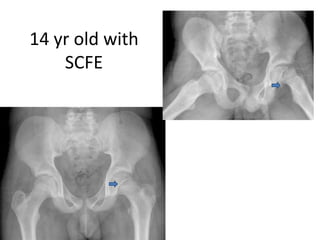

14 yr old with

SCFE

Slipped capital femoralepiphysis (SCFE) The ball at the upper end of the femur (thigh bone) slips off in a backward direction. Due to weakness of the growth plate. Most often, it develops during periods of accelerated growth, shortly after the onset of puberty is an unusual disorder of the adolescent hip It is not rare. TYPES: • Stable SCFE. This is referred to as a "mild slip," which causes some stiffness or pain in the knee or groin area, and possibly a limp • Unstable SCFE. This is a more severe usually much more painful, unable to bear weight on the affected side, ROM severely limited, leg turns outward, is more serious because it can restrict blood flow to the hip joint, leading necrosis

Slipped capital femoralepiphysis (SCFE) Risk Factors: • The cause of SCFE is unknown. It occurs two to three times more often in males than females. A large number of patients are overweight. • In most cases, is a slow and gradual process. However, it may occur suddenly and be associated with a minor fall or trauma. • Symptomatic SCFE, treated early and well, allows for good long-term hip function Symptoms: • Weeks or months of hip or knee pain and an intermittent limp • walks with a limp. In certain severe cases, unable to bear any weight on the affected leg • affected leg is usually turned outward in comparison to the normal leg • affected leg may appear to be shorter

Slipped Capital FemoralEpiphysis (SCFE) Normal anatomy Types of SCFE

14 yr oldwith SCFE